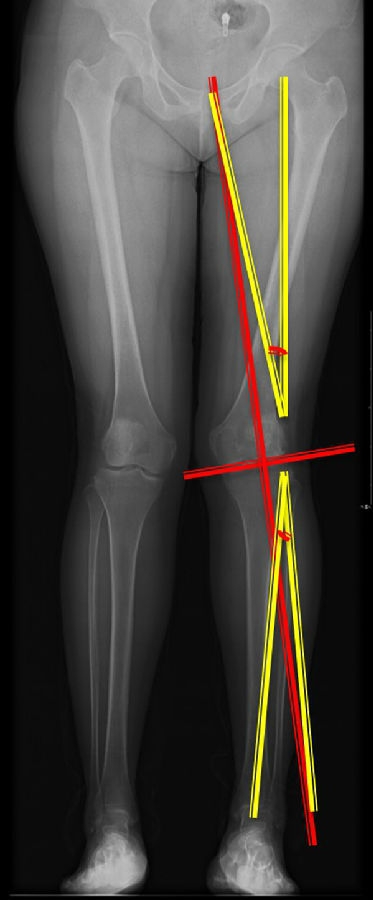

步骤三:设定目标力线

以关节线为基准参考线,设定目标力线与关节线垂直。

步骤四:确定合页位置和截骨线方向

此患者计划股骨内侧闭合楔,胫骨内侧开放楔。

步骤五:Miniaci法测量角度

以股骨侧合页为旋转中心,以股骨头中心到合页的距离为半径,进行旋转,直到该线段与目标力线相重合,此时重合角度即为股骨需要闭合的角度,同时胫骨侧也能计算出开放的角度。此患者需要股骨闭合14°,胫骨开放8°。